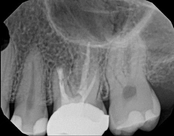

Non-surgical root canal treatment:

Before

Immediately After

6-month follow-upThis patient presented with pain when chewing. Diagnostic testing was done and determined it was the lower molar. The diagnosis was: pulpal necrosis, symptomatic periradicular periodontitis. Root canal treatment was performed with laser disinfection. The tooth had a crown and we accessed the tooth through the crown. We saved the tooth and the crown.